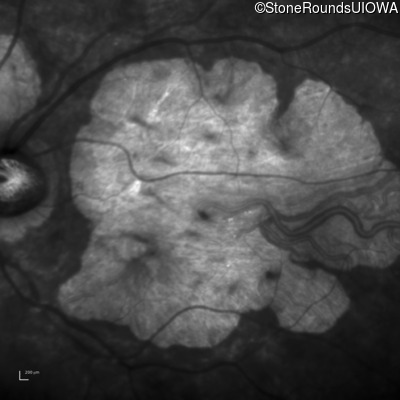

Visit at age: 76 years

Infrared Fundus Photograph - Right - 20/150

Exemplar